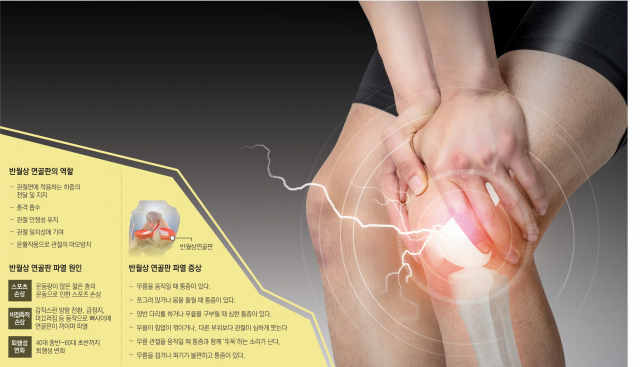

◆반월상 연골판 손상의 증상

해부학적으로 반월연골판의 가장자리 부위를 제외한 안쪽 3분의2 가량은 혈관과 신경이 분포하지 않기 때문에, 단순히 이 부위가 파열됐다고 통증을 일으키는 것은 아니다.

일반적으로 통증은 무릎을 구부리고 펼 때나 회전 동작을 할 때에 파열된 조각이 대퇴골과 경골 사이의 관절면 사이에 끼어 당겨지게 되는데, 이 때 원래 찢어지지 않았던 부위까지 같이 당겨지기 때문에 반월연골판의 가장자리에 분포하는 신경이 자극돼 통증이 발생하는 것으로 여겨진다.

파열의 크기가 커서 끼이는 조각이 클수록 통증도 더 심해지며, 때에 따라서는 큰 파열된 조각이 관절면 사이에 단단히 껴 빠지지 않으면서 생기는 통증으로 무릎을 펴지도 구부리지도 못하는 잠김 현상이 발생하기도 한다.

반월연골판이 파열되면 충격을 흡수하고 체중 부하를 분산해 무릎 관절연골을 보호했던 원래의 기능이 소실돼 관절연골의 퇴행성 변화가 촉진되며, 퇴행성 관절염의 진행 속도가 빨라지게 된다.

반월상 연골판 손상의 진단은 손상부위 통증 및 파열된 관절선의 압통, 관절 부종, 관절 운동 시 발생하는 마찰음, 잠김 현상, 반월연골판 자극 검사 등의 증상과 신체검사로 진단할 수 있으며, 자기공명영상(MRI)을 촬영해 반월연골판 파열 유무 및 부위, 형태, 크기를 확인할 수 있다.